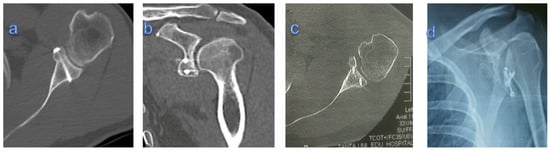

3.2. Radiological Results

The coracoid graft was correctly positioned in sixteen patients (76.2%), whereas in five cases (23.8%), the coracoid position was wrong: in two patients it was too lateral, in the other two, it was too inferior, and in one case it was too medial. The screw insertion was also mal-positioned in two cases, but there was no screw breakage, loosening, and impingement (Figure 4). In three patients, the coracoid graft showed non-union and partial resorption at the end of follow-up.

Figure 4. (a,b) Axial and coronal CT showing flushed united congruent graft; (c) axial CT showing too-lateral graft; (d) X-ray showing too-low graft and screw malposition.